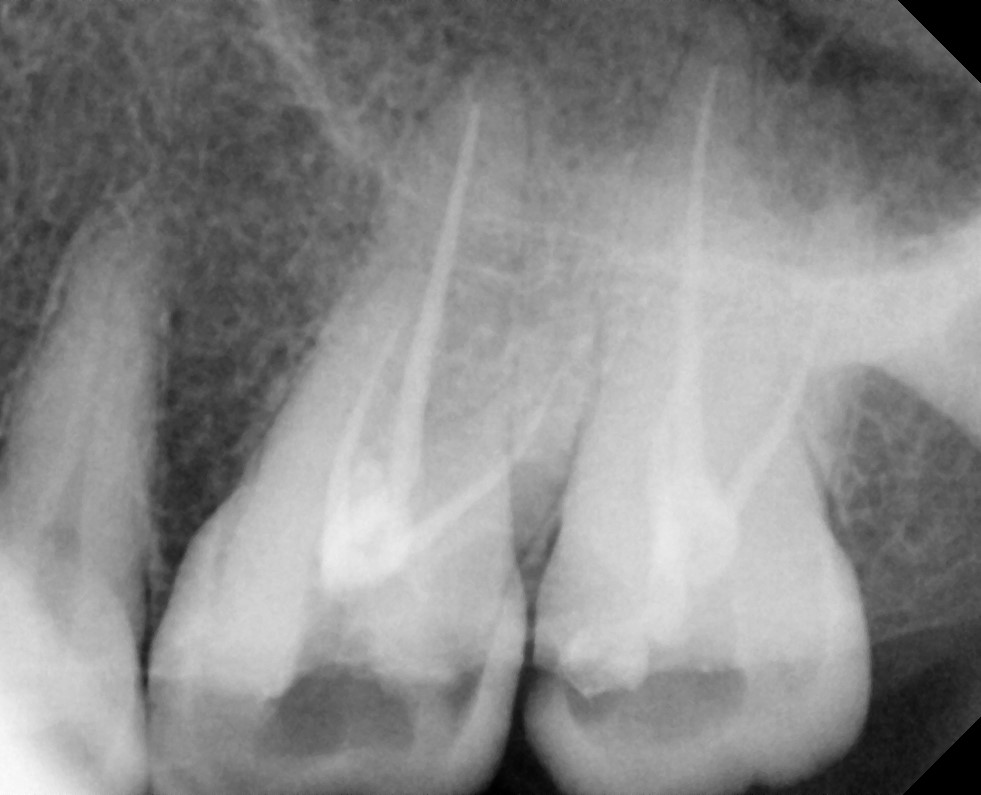

Extirpation:Initial clean to control bacterial infection.

• When the pulp of the tooth is infected, there is pain.

• A diagnosis is made for the tooth with percussion, palpation and cold tests and an x-ray.

• Once it is confirmed that the tooth requires root canal treatment.

• After anesthesia given, a small opening on the top of the tooth to clean the root canal with small files

• We rinse the tooth with antibacterial solutions to eliminate the bacteria

• We leave medicine inside the tooth and place a temporary filling on top

Gallery